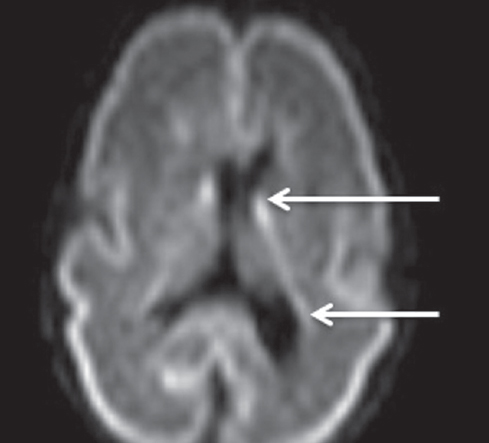

Как видно из таблицы, при выполнении МР-исследования в ПКВ 27–32 недели герминальный матрикс визуализировался у восьми недоношенных детей на ДВИ в виде усиления МР-сигнала вдоль боковых стенок боковых желудочков мозга, а также вдоль передних рогов над хвостатыми ядрами с обеих сторон (рис. 4). На Т2 ВИ герминальный матрикс достоверно выявлен у семи новорожденных (рис. 5). На Т1 ВИ герминальный матрикс достоверно выявлен у двух новорожденных (рис. 6). На последовательностях FLAIR герминальный матрикс не визуализировался.

Рис. 4. МРТ головного мозга недоношенного ребенка (ПКВ 28 недель), ДВИ, аксиальная проекция. Визуализируется гиперинтенсивный МР-сигнал от герминального матрикса в проекции наружных отделов боковых желудочков (отмечен стрелками)

Fig. 4. MRI of preterm newborn (PCA 28 wks.), DWI, axial plane. Hyperintensive MR-signal from the germinal matrix in the projection of the external parts of lateral ventricles (marked by arrows)

У новорожденных, которым МРТ проводили с 33-й по 34-ю неделю ПКВ, герминальный матрикс визуализировался у двух пациентов на ДВИ в виде слабого повышения МР-сигнала вдоль боковых стенок боковых желудочков мозга (рис. 7). На остальных импульсных последовательностях герминальный матрикс не определялся.

Рис. 7. МРТ головного мозга недоношенного ребенка (ПКВ 34 недели). ДВИ, аксиальная проекция, герминальный матрикс визуализируется вдоль наружных стенок боковых желудочков (отмечен стрелками)

Fig. 7. MRI of preterm newborn (PCA 30 wks.), DWI, axial plane. The germinal matrix is visualized along the external walls of the lateral ventricles (marked by arrows)